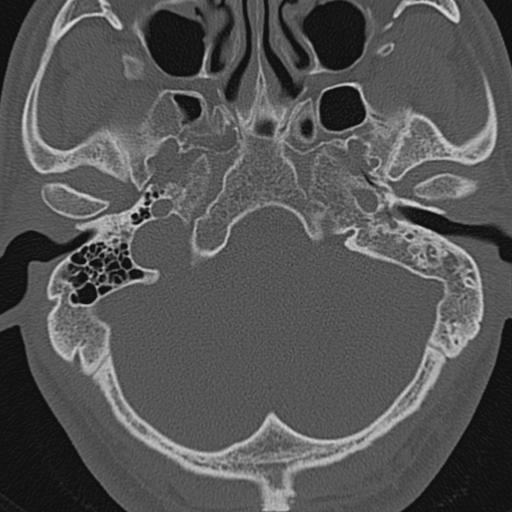

以下是引用zxl51642在2009-8-25 13:37:00的发言:[br]1、左侧慢性硬化型中耳乳突炎(中耳鼓室腔及听小骨受累),并胆脂瘤形成;2、左侧外耳道软组织密度影填塞,考虑炎性肉芽肿,建议结合临床;3、右侧颈静脉窝较左侧明显扩大,不排除颈静脉球瘤,建议mr进一步检查。

以下是引用随光逐影在2009-8-25 19:05:00的发言:[br]1)左侧慢性中耳乳突炎(肉芽肿或胆脂瘤形成),左侧外耳道炎性肉芽肿。2)右侧颈静脉球高位。